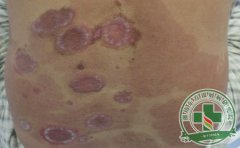

寻常型点滴状牛皮癣是一种非常难以祛除的皮肤病,对患者身体上会造成巨大的影响,寻常型点滴状牛皮癣在当今...[详细]

很多牛皮癣患者对牛皮癣病情并不是十分了解,有很多牛皮癣患者都是等到自己的牛皮癣病情到了相当严重的地...[详细]